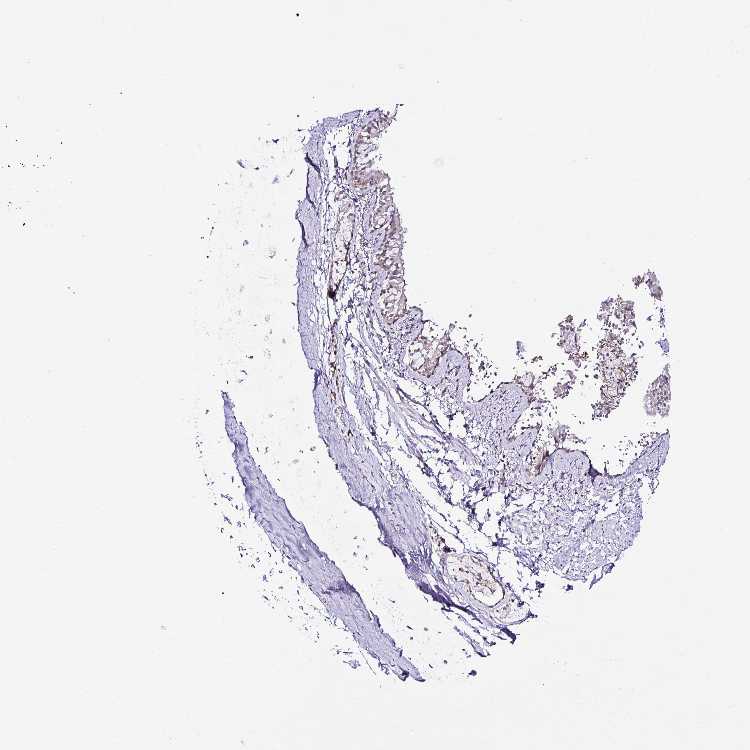

ADIPOSE TISSUE - Antibody stainingi

Antibody staining in the annotated cell types in the current human tissue is reported as not detected, low, medium, or high, based on conventional immunohistochemistry profiling in selected tissues. This score is based on the combination of the staining intensity and fraction of stained cells.

Each image is clickable and will lead to virtual microscopy that enables deeper exploration of all samples and also displays staining intensity scores, fraction scores and subcellular localization as well as patient and tissue information for each sample.

Antibody HPA048972Antibody CAB017038

Adipocytes Not detectedLow